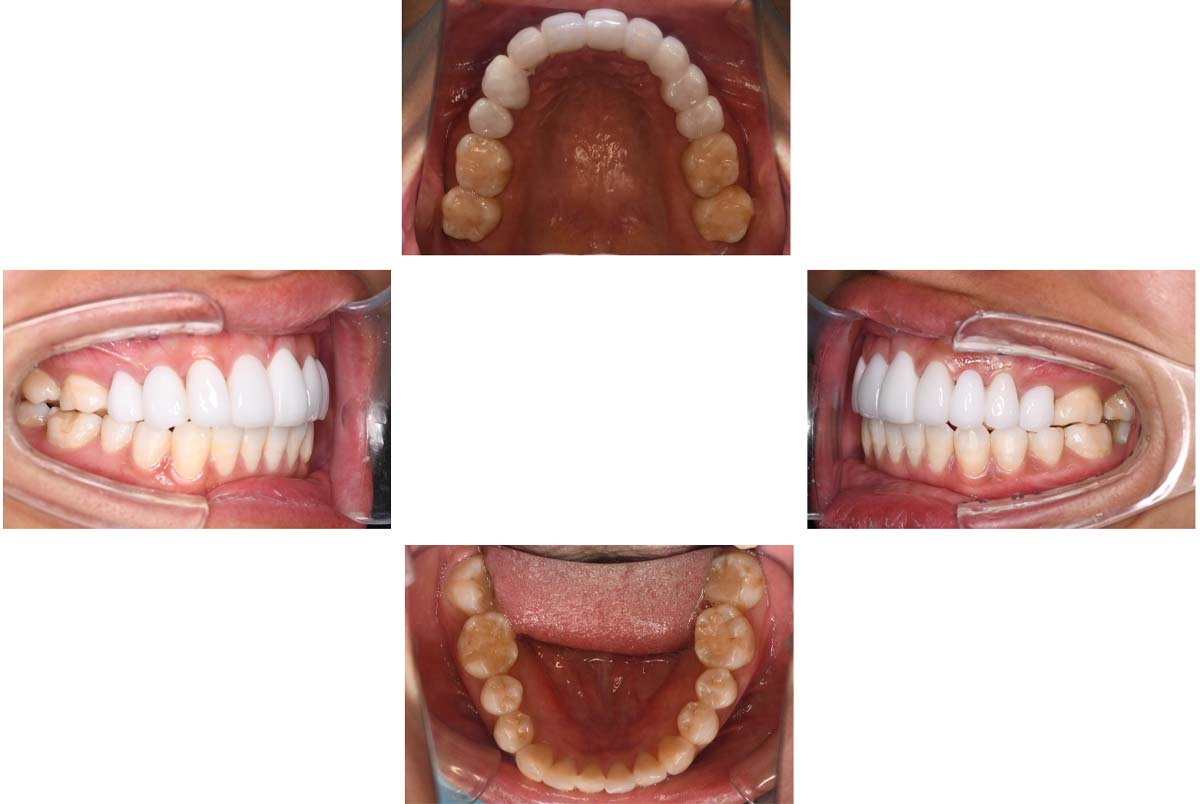

| 治療内容 | ①スプリントを装着 ②副子を装着 ③2024年4月 口腔内反映開始 ④副子を入れた状態の所まで咬合を挙上 (バイトアップ) ⑤2024年5月 上顎前歯部8本に仮歯(TEK) を装着 |

バイトアップ後

![]() |